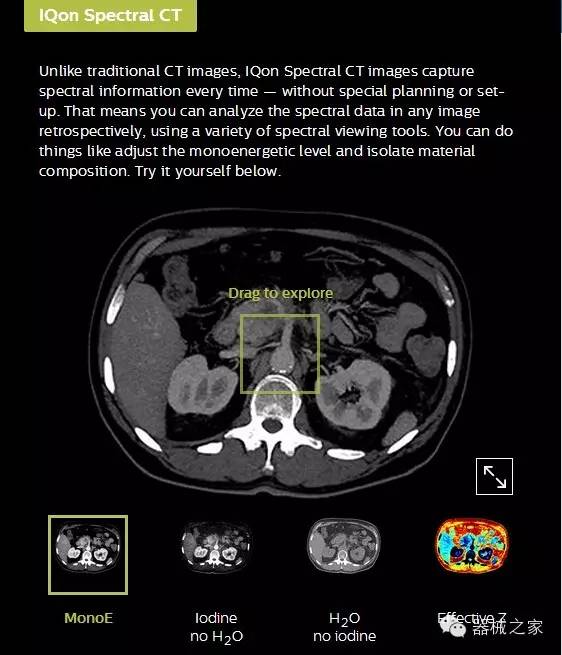

IQon光譜CT能夠按照需求提供光譜量化和工具,并能通過簡單工作流程、在低劑量下對結(jié)構(gòu)進行定性分析

IQon光譜CT -- 是業(yè)界首臺以探測器為成像基礎(chǔ)的光譜CT,它可以在單次常規(guī)掃描下獲得傳統(tǒng)解剖影像及光譜功能影像。不僅可以提供精準(zhǔn)的診斷信息,還可簡化工作流程、在低劑量下完成定量與定性分析。